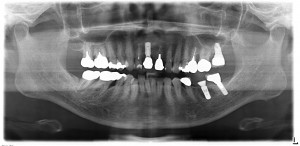

インプラント埋入後のパノラマレントゲンですが、計画通りに埋入されています。